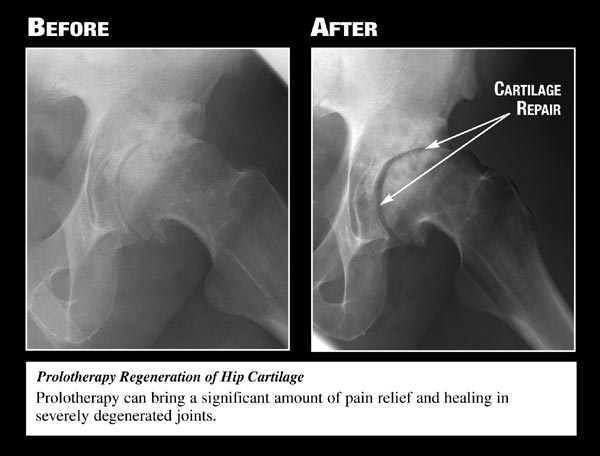

Used with permission

from Ross A Hauser, MD,

www.caringmedical.com.

range of motion returns, and cartilage degeneration slows

down.